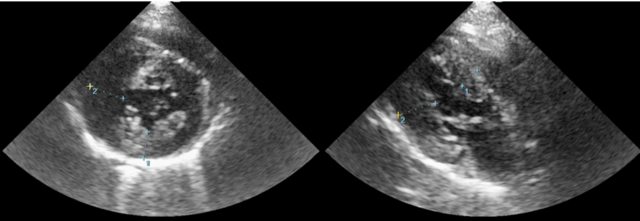

肥大型心筋症

他の病気の検査の一環として、心臓の検査をした際に心筋の肥厚が認められました。

上記の検査は全て問題なく、心筋の負担を調べる検査(心臓バイオマーカー:NT-proBNP,cTn)も高値でしたので肥大型心筋症と診断しました。

幸い心臓疾患による症状もなく、心臓にかかっている負担も軽度でしたので、心拍数を少し抑える薬のみで注意深く経過観察をしていく事になりました。